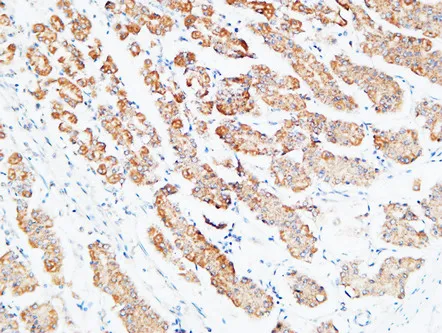

MPO Rabbit Polyclonal Antibody

Cat: APRab14056

Size1:50μl Price1:$118

Size2:100μl Price2:$220

Size3:500μl Price3:$980

Size2:100μl Price2:$220

Size3:500μl Price3:$980